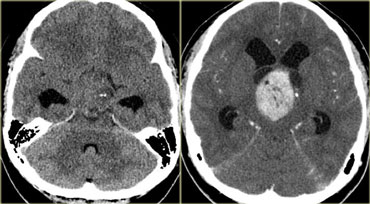

Ring enhancement

Ring enhancement is seen in metastases and high-grade gliomas.

It is also seen in non-tumorous lesions like abscesses, some MS-plaques and sometimes in an old hematomas.

On the left three different ring enhancing lesions.